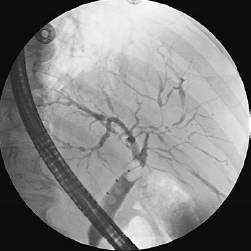

While on the inpatient service, the patient is noted to have a serum alkaline phosphatase of 380 U/L and a bilirubin of 2.4 mg/dL. An ERCP is performed, and the following cholangiogram is obtained. In addition to ulcerative colitis, the patient likely has what other illness?

Oral corticosteroids are a mainstay of firstline treatment for moderate-to-severe ulcerative colitis. Starting doses of 40 mg PO daily of prednisone, with a slow taper, are often effective in reducing colonic inflammation, although some patients are unable to wean steroids or maintain remission once achieved. The patient does not have dysplasia in any biopsy specimens, nor does he have signs of systemic toxicity, so a colectomy would be premature. Oral metronidazole is ineffective in ulcerative colitis. Cortisone enemas would be helpful if the patient had isolated left-sided disease, but it is doubtful that enema therapy would reach his hepatic flexure. Intravenous cyclosporine would be used in severe colitis as a last measure before colectomy but this patient is not yet sick enough to warrant such therapy. PSC occurs in approximately 3% of patients with ulcerative colitis and is its major liver complication. It is a chronic inflammatory condition of the biliary tree. It can typically manifest with elevated alkaline phosphatase and bilirubin levels, and results in diffuse stricturing and pruning of the biliary tree. Wilson disease, hereditary hemochromatosis and alpha-1 antitrypsin deficiency are not associated with ulcerative colitis and are not cholestatic liver diseases. Primary biliary cirrhosis could account for these laboratory findings, but is rare in both males and patients with ulcerative colitis. Patients with PSC are at increased risk of developing cholangiocarcinoma but not the other liver tumors mentioned. Patients with celiac sprue are at increased risk for small bowel cancers (adenocarcinoma, lymphoma). Patients with FAP are at increased risk to develop desmoid tumors.